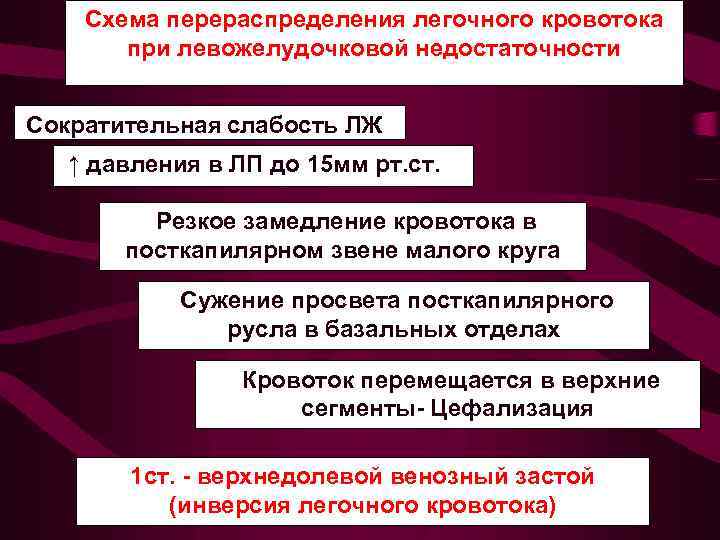

Схема перераспределения легочного кровотока при левожелудочковой недостаточности Сократительная слабость ЛЖ ↑ давления в ЛП до 15 мм рт. ст. Резкое замедление кровотока в посткапилярном звене малого круга Сужение просвета посткапилярного русла в базальных отделах Кровоток перемещается в верхние сегменты- Цефализация 1 ст. - верхнедолевой венозный застой (инверсия легочного кровотока)

Схема перераспределения легочного кровотока при левожелудочковой недостаточности Сократительная слабость ЛЖ ↑ давления в ЛП до 15 мм рт. ст. Резкое замедление кровотока в посткапилярном звене малого круга Сужение просвета посткапилярного русла в базальных отделах Кровоток перемещается в верхние сегменты- Цефализация 1 ст. - верхнедолевой венозный застой (инверсия легочного кровотока)

1 -верхнедолевой Усилен легочный рисунок в венозный застой верхних долях, укрупнен колибр (инверсия верхнедолевых вен. легочного Корни легких обычной величины, кровотока) но может отмечаться его незначительное расширение и увеличение колибра ортогональных теней сосудов в центральных отделах корня. Среднее давление в левом предсердии от 10 до 15 мм рт. ст.

1 -верхнедолевой Усилен легочный рисунок в венозный застой верхних долях, укрупнен колибр (инверсия верхнедолевых вен. легочного Корни легких обычной величины, кровотока) но может отмечаться его незначительное расширение и увеличение колибра ортогональных теней сосудов в центральных отделах корня. Среднее давление в левом предсердии от 10 до 15 мм рт. ст.

Схема перераспределения легочного кровотока при левожелудочковой недостаточности Сократительная слабость ЛЖ ↑ давления в ЛП от15 до 25 мм рт. ст. Резкое замедление кровотока в посткапилярном звене малого круга Диффузное расширение посткапилярного русла 2 ст. - диффузный венозный застой

Схема перераспределения легочного кровотока при левожелудочковой недостаточности Сократительная слабость ЛЖ ↑ давления в ЛП от15 до 25 мм рт. ст. Резкое замедление кровотока в посткапилярном звене малого круга Диффузное расширение посткапилярного русла 2 ст. - диффузный венозный застой

2 - диффузный венозный застой Среднее давление в левом предсердии от 15 до 25 мм рт. ст. Усилен венозный легочный рисунок во всех отделах легких до перифирии. Увеличено количество сосудистых теней на единицу площади легочного поля. Корни легких расширены структура их не диффе ренцируется. Отмечается нерезкость контуров корня и сосудов.

2 - диффузный венозный застой Среднее давление в левом предсердии от 15 до 25 мм рт. ст. Усилен венозный легочный рисунок во всех отделах легких до перифирии. Увеличено количество сосудистых теней на единицу площади легочного поля. Корни легких расширены структура их не диффе ренцируется. Отмечается нерезкость контуров корня и сосудов.